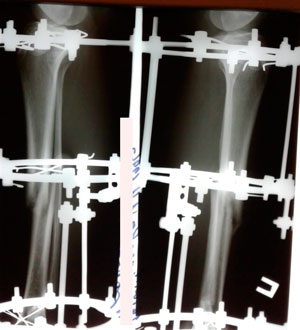

Рентген перед снятием аппаратов

IMG_6527-17-10-19-04-49.JPG

IMG_6526-17-10-19-04-49.JPG

Дата операции - 12.07.2019г.

Дата снятия аппаратов - 17.10.2019г.

Срок сращения - 95 дней.